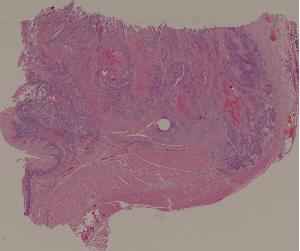

9. Healing of skin by first intention